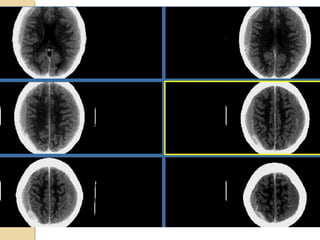

DIFFUSE AXONAL INJURYDIFFUSEAXONAL INJURY Rarely detected on CT ( 20% of DAI lesions are hemorrhagic) MRI:T1,T2,T2 GRE, SWI

• 27.

DAIDAI Due to acceleration/decelerationto whtie matter + hypoxia Patients have severe LOC at impact Grade 1: axonal damage in WM only -67% Grade 2:WM + corpus callosum (posterior > anterior) – 21% Grade 3:WM + CC + brainstem

• 28.

DAIDAI Hours: ◦ hemorrhages andtissue tears ◦ Axonal swellings ◦ Axonal bulbs Days/weeks: clusters of microglia and macrophages, astrocytosis Months/years:Wallerian degeneration